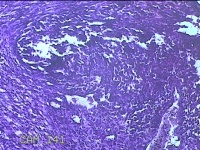

左卵巢囊肿

性别

女

年龄

32岁

临床诊断

左卵巢巧克力囊肿破裂

一般病史

下腹疼痛2天,加重10小时。

标本名称

大体所见

灰白暗红色囊壁样组织5.3x2x1.3cm一堆,表面糜烂,因已切开,囊内容物已流失,囊壁厚0.1cm。

图2